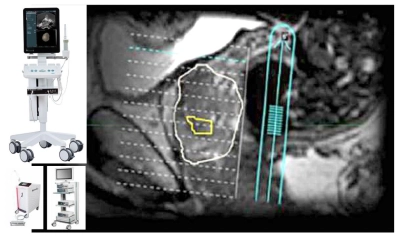

Puncția biopsie prostatică prin fuziune (fusion biopsy) este o tehnică pentru detectarea cancerului de prostată la pacienții suspecți, cu o acuratețe superioară biopsiei clasice. Tehnica presupune fuzionarea imaginilor obținute la investigația prin rezonanță magnetică multiparametrică, unde se evidențiază o zonă suspectă, cu imaginea ecografică obținută în timp real la ecograful de ultimă generație bk3000, specializat pe Urologie. Suprapunerea se face prin intermediul unui software special (bkFusion) și se efectuează așa numită „sinteză”.

Fuziunea realizată de ecograful bk3000 oferă o hartă tridimensională a prostatei și a leziunilor prostatice suspecte și ghidează acul de biopsie direct în zonele suspecte de cancer. Astfel, utilizarea biopsiei de fuziune se asociază cu o detectare crescută a cancerului de prostată semnificativ clinic, comparativ cu biopsiile sistematice. Totodată, biopsiile țintite (fusion biopsy) sunt efectuate rapid și cu riscuri mai mici decât în cazul altor proceduri similare. Chiar mai important, diagnosticul este foarte precis și sunt evitate astfel cazurile în care ar fi fost necesară o repuncționare. Procedura se realizează doar cu anestezie locală și nu necesită internare.